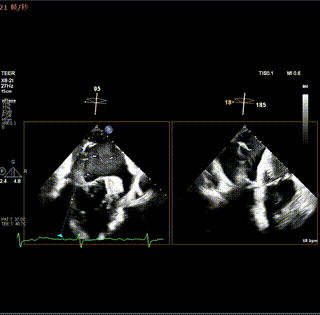

術前XPLANE: 3區大量偏心性反流

患者全麻后,在經食道超聲心動圖與X射線引導下,在卵圓窩中、后部行房間隔穿刺,瓣上高度約4.4cm。隨后送入22F大鞘及長寬型號瓣膜夾系統,在超聲輔助下,術者精細調整,系統定位3區病變并反復確認對準返流束來源位置。

確認夾臂方向與彈道后,將瓣膜夾送至瓣下,進行瓣葉抓捕并關閉夾子進行評估。經超聲評估,存在一束殘余返流,后再置入一枚長窄夾子,超聲評估無殘余返流且瓣葉抓捕長度充足,組織橋穩定,跨瓣壓差1 mmHg,肺靜脈逆流消失,遂將瓣膜夾釋放,手術成功。